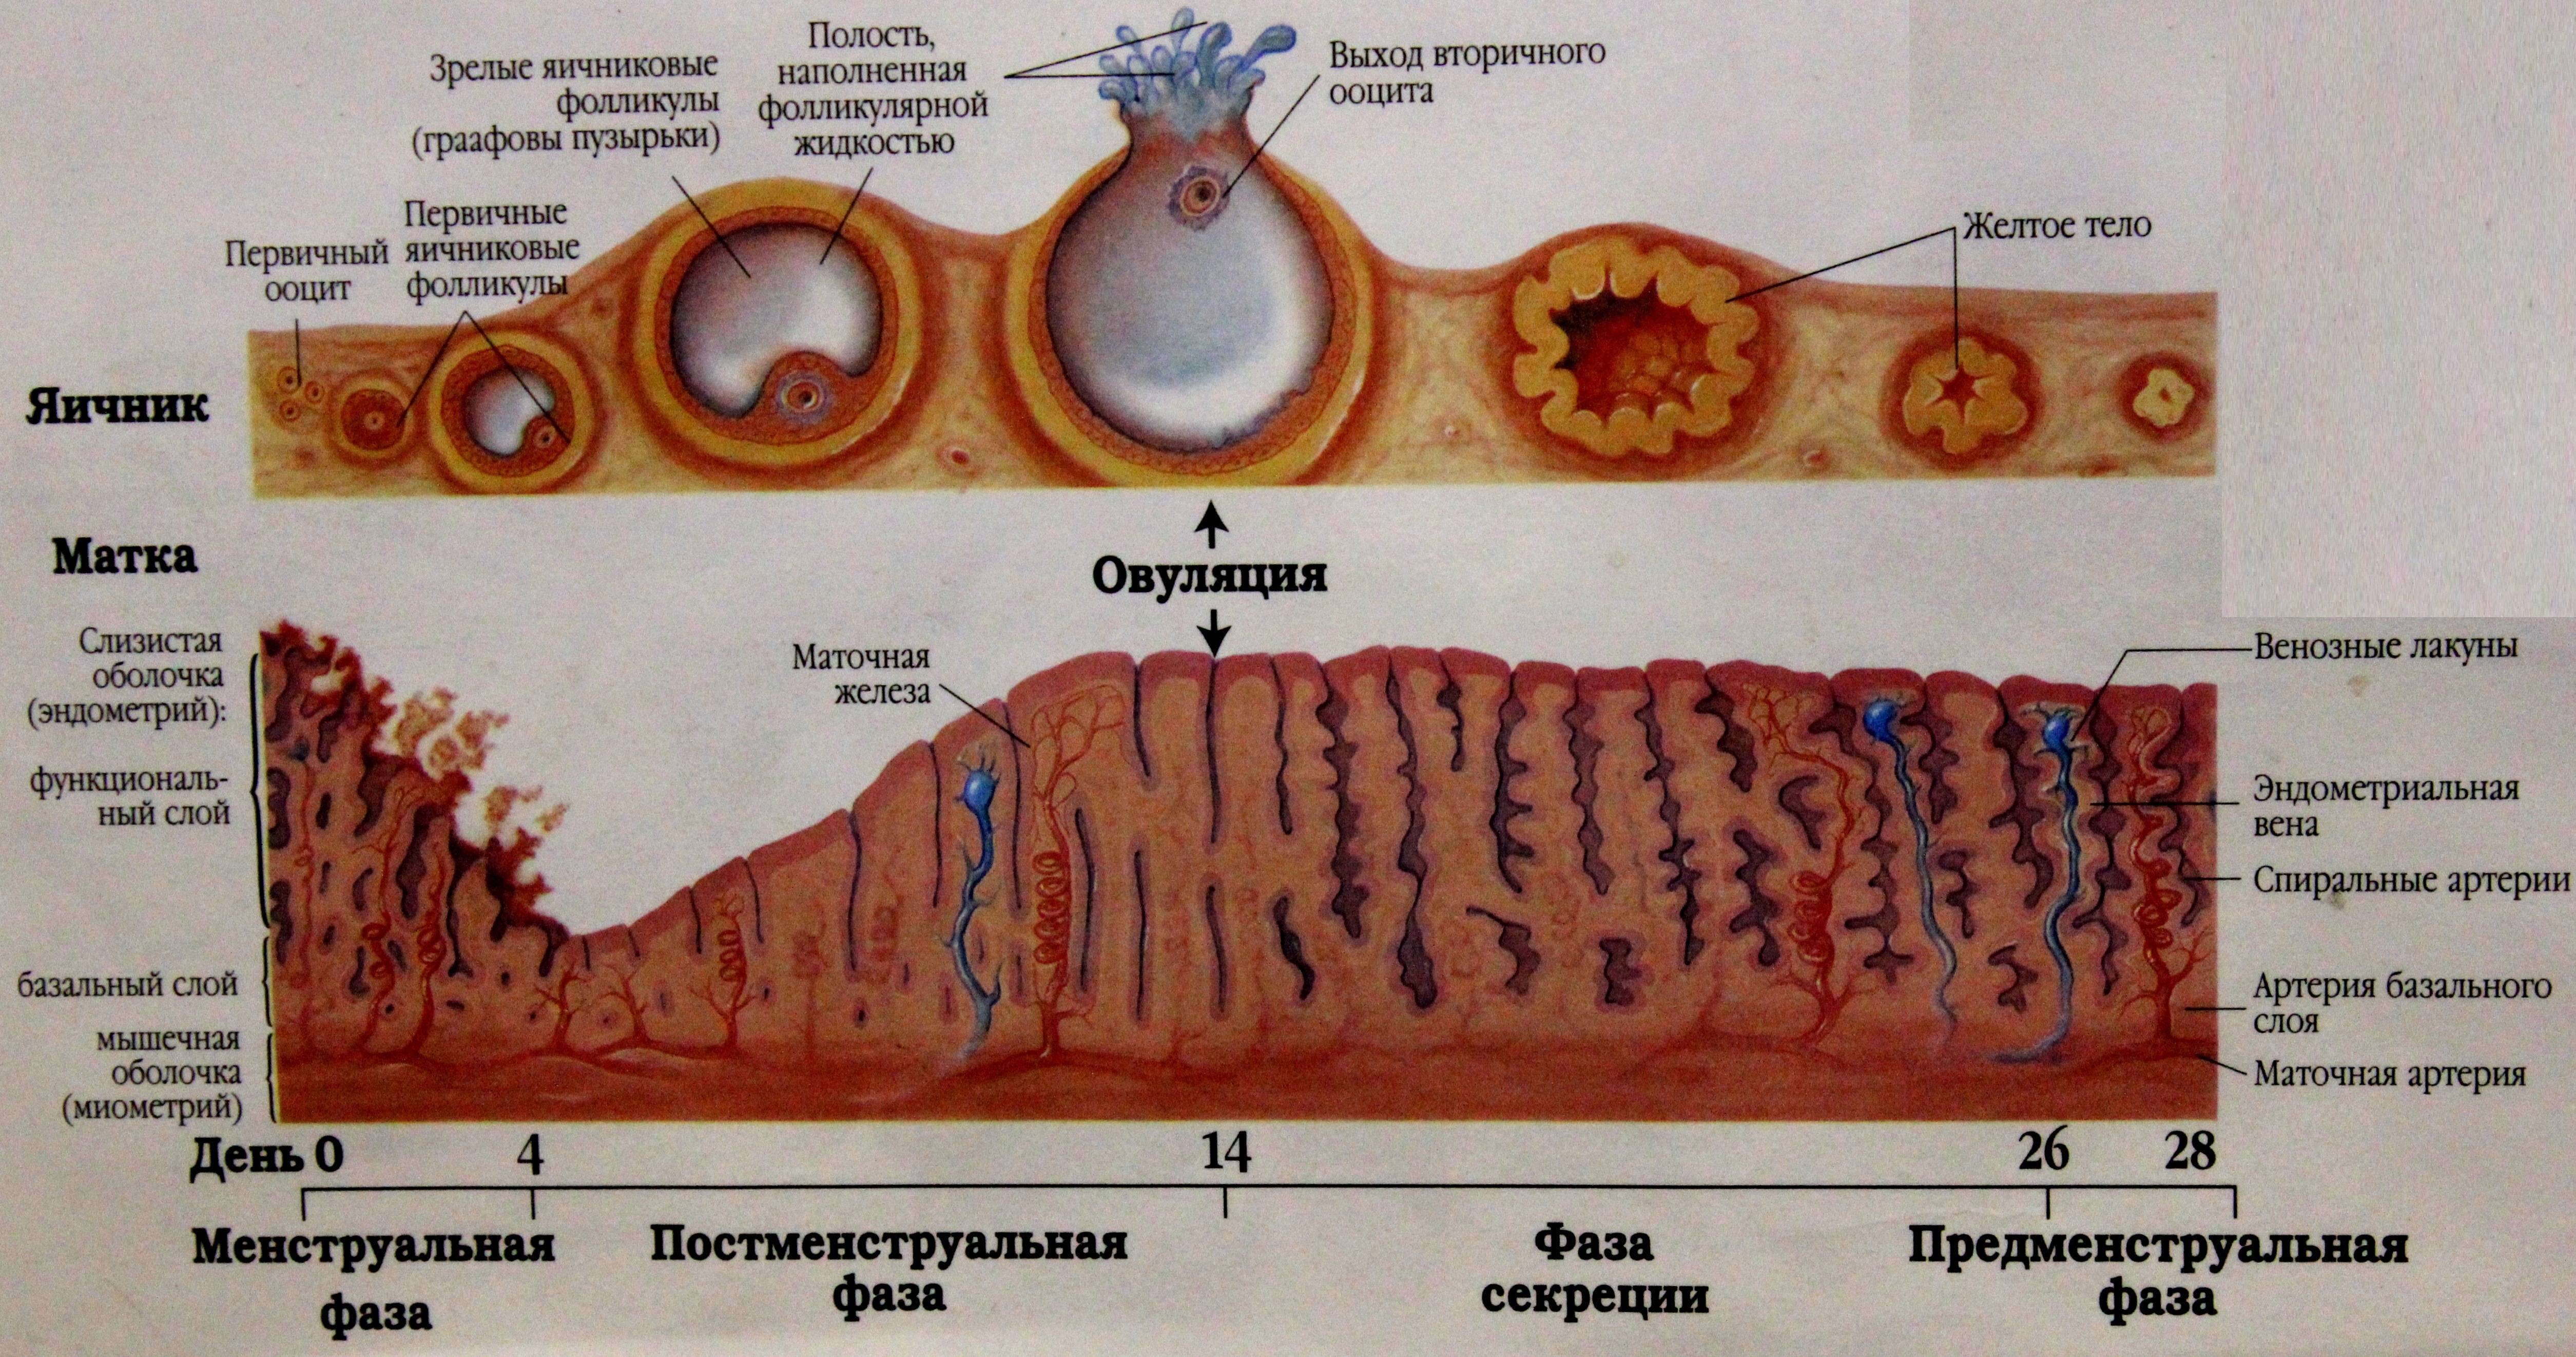

Созревание фолликула в яичнике: этапы и процессы